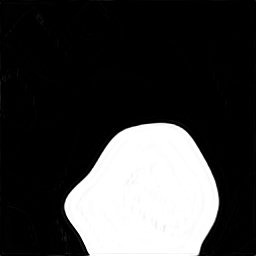

A few sample images and the corresponding masks of the polyp dataset in HyperKvasir are shown in Fig 2. The polyp images are RGB images. The masks of the polyp images are single-channel images with white () for true pixels, which represent polyp regions, and black () for false pixels, which represent clean colon or background regions. In this dataset, there are different sizes of polyps. The distribution of polyp sizes as a percentage of the full image size is presented in the histogram plot in Fig 3, and we can observe that there are more relatively small polyps compared to larger polyps. Additionally, a subset of this dataset was used to prove that the performance of segmentation models trained with small datasets can be improved using our SinGAN-Seg pipeline, and the whole dataset was used to show the effect of using SinGAN-Seg generated synthetic images instead of a large dataset which has enough data to train segmentation models. In this regard, this dataset was used for two purposes:

In total, we have generated synthetic polyp images and the corresponding masks. SinGAN-Seg generates random samples with high variations when the input scale is . This variation can be easily recognized using the standard deviation (SD) and the mean mask images presented in Fig 5. The mean and SD images were calculated by stacking the generated mask images corresponding to the synthetic images related to a real image and calculating pixel-wise std and mean. Bright color in std images and dark color in mean images mean low variance of pixels. In contrast, dark color in std and bright color in mean images reflect high variance in pixel values. By investigating Fig 5, we see that small polyp masks have high variance compared to the large polyp mask as presented in the figure.